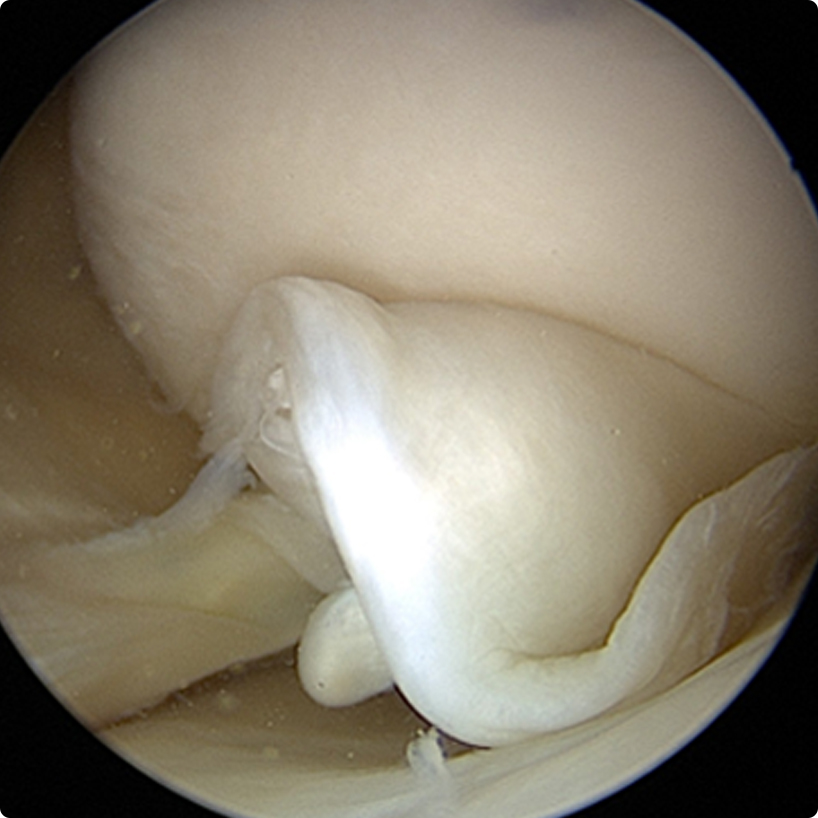

Yırtık oluştuğunda dizde ağrı, hareket kısıtlılığı, şişlik, takılma, kilitlenme gibi yakınmalar görülür. Özellikle genç yaş grubunda oluşan yırtıklarda daha mekanik şikayetler (takılma, kilitlenme gibi) ön plandadır. Menisküsteki yırtık hareketli ise eklem aralığına sıkışıp dizi kilitleyebilir (şekilde eklemi kilitleyebilen hareketli yırtık menisküs parçası görülmektedir). Bu durumda hasta genellikle dizini tam uzatamaz ve bükmesi de sınırlıdır. Daha ileri yaşlardaki yırtıklarda ise süreğen, hareketler sırasında belirginleşen, yaygın bir ağrı söz konusudur.